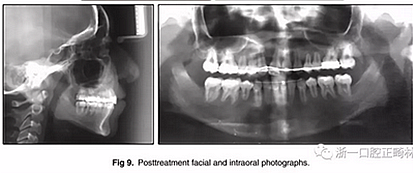

兩年半后,在上下牙弓上均實現(xiàn)了間隙關(guān)閉,并且使用0.017×0.025英寸的不銹鋼弓絲進行咬合精細調(diào)整(圖8)。去除托槽后,上下頜采用舌側(cè)弓進行保持(圖9)。